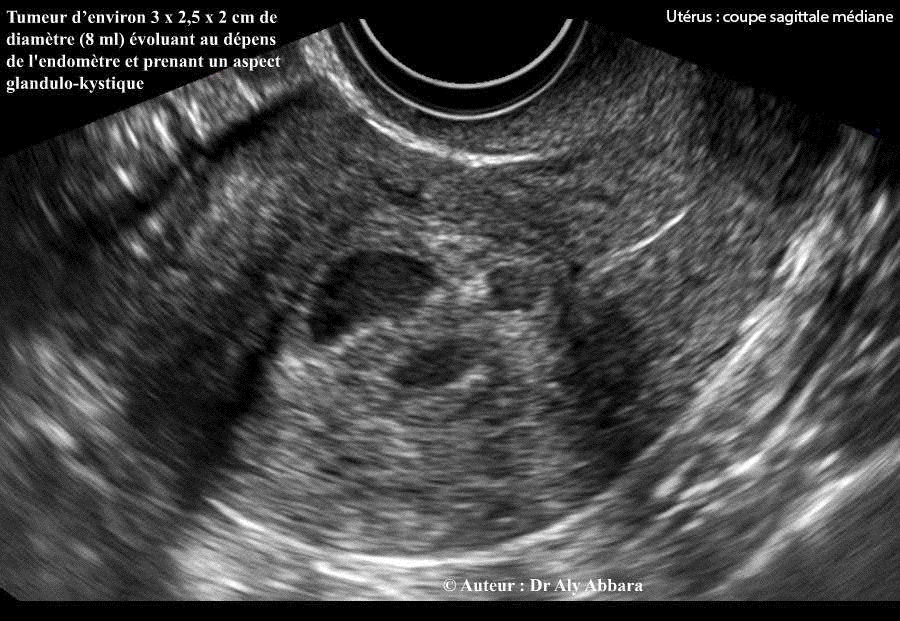

Kyste Polype endométrial par hyperplasie bénigne glandulo-kystique

Polype endométrial hyperplasique glandulo-kystique évoluant au dépens de l'endomètre de la postérieure de la cavité utérine

Images échographiques montrant une formation ovoïde évoluant au dépens de l'endomètre et prenant le forme d'une tumeur (polype) mesurant 26,6 x 19,8 x 29,1 mm (soit 8 cm3) ; elle est composée de multiples micro logettes tapissées par un revêtement et séparées par des cloisons parcourues par des micro-vaisseaux sanguines (aspect glandulo-kystique).

• L'hystéroscopie montre qu'il s'agit d'une formation tumorale (polype) d’environ 3 x 2,5 x 2 cm de diamètre évoluant au sein de la paroi postérieure de la cavité utérine avec une large base d’insertion (polype sessile) ; elle est de consistance fibreuse évoquant le diagnostic de fibrome endocavitaire utérin.